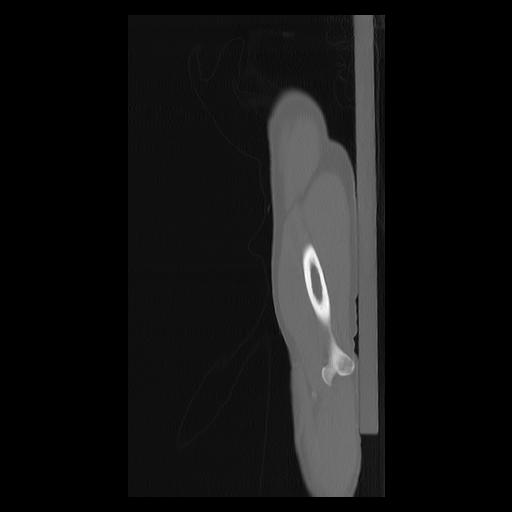

33 PULMON,CE,Sagittal,3.000,PULMON,Sagittal,